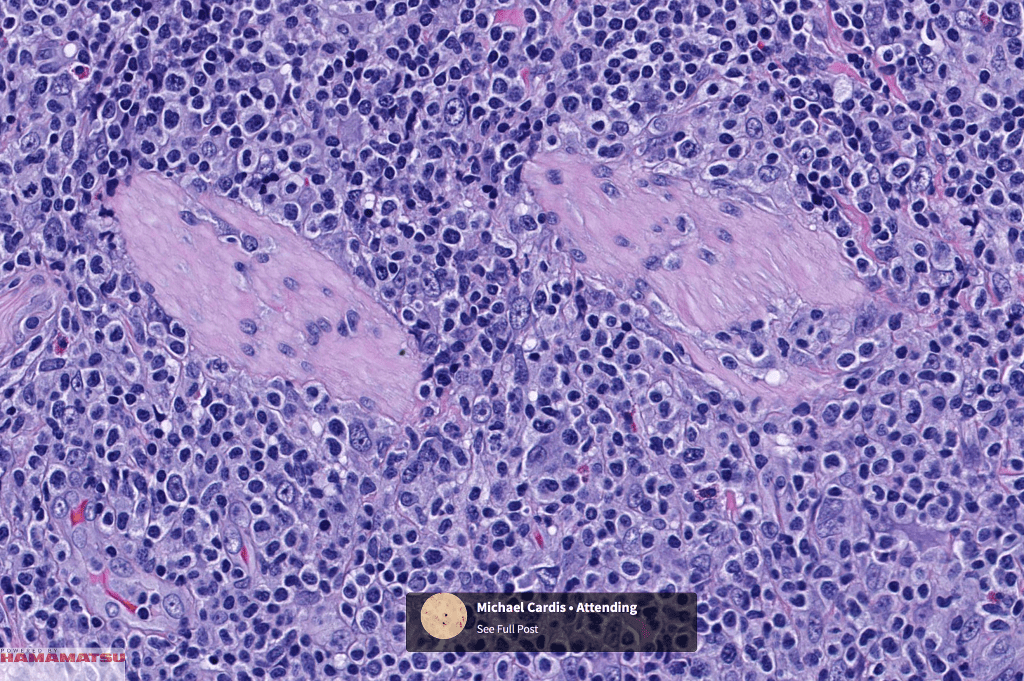

•Type E: angioinvasive & angiodestructive

•Variable epidermal necrosis, epidermotropism, edema, hemorrhage & vasculitis/thrombosis

•CD4, CLA, MUM1 +ve

•CD8-ve (except for types D & E variants)

•Granzyme-B, TIA-1 & perforin +ve)